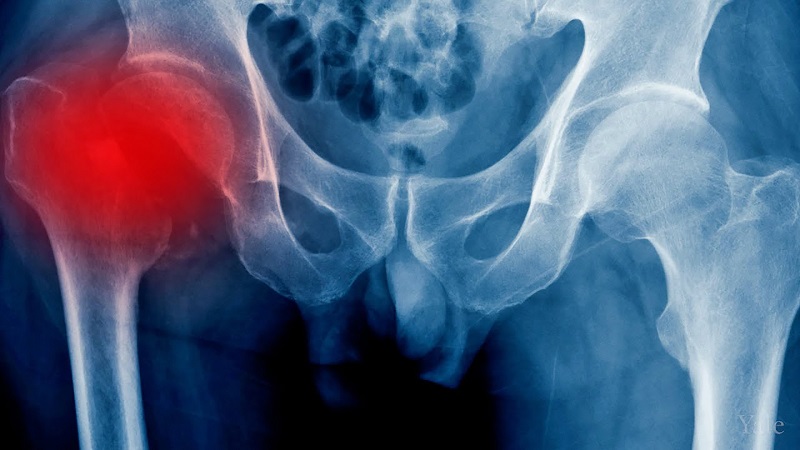

Avascular necrosis harms bone tissue. Blood flow reduces within the hip. Bone cells without supply soon fail. Arthritis also wears the cartilage. The smooth surface becomes rough. Every movement then brings harsh pain. The body weakens further each day. Patients often lose mobility and peace. Simple walks feel like hard work. Conventional methods mask pain briefly. Surgery brings risk and long recovery. Stem cell care seeks another path. This path supports internal growth. Healthy tissue can then return. Hope rises for a better life.